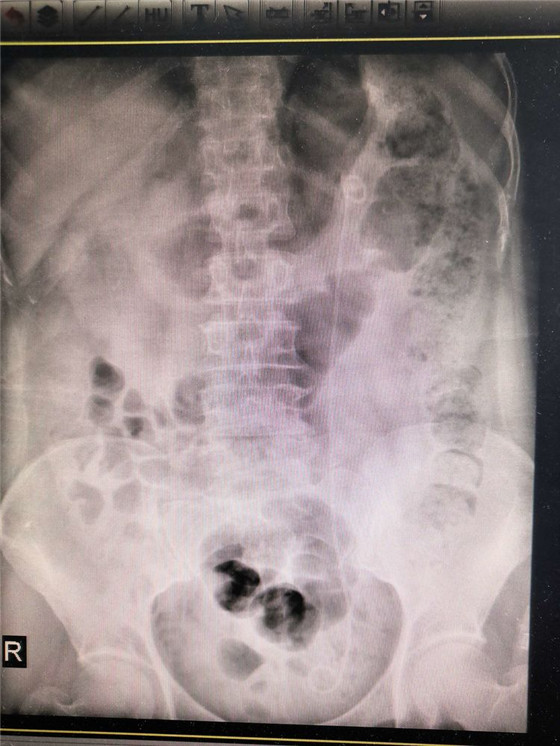

患者术后第二天复查尿路平片